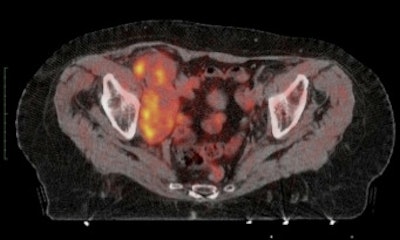

The field of molecular imaging is experiencing an impressive period of innovation and growth. PET is becoming a leading tool to investigate changes in the living human body, thanks to the availability of reliable probes and the introduction of new and more specific radiopharmaceuticals, which hopefully can selectively image different pathways of a tumor's biology.

Modern PET often involves hybrid imaging: PET/CT sets the standard for functional imaging, and PET/MR systems are emerging from research apparatus to clinical tools.

One of the best ways to attract young people to a research field is to make its characteristics visible and underline its strength in improving healthcare. Recent developments in molecular imaging fit well with this goal. Besides FDG-PET, more advanced techniques are entering the clinical arena. Evaluation of response in lymphoma and solid tumors, along with the integration of PET images in radiation therapy planning, are just a couple of strong examples of new applications of FDG PET/CT in oncology. Infection imaging is another emerging field, and improvements are being made in diagnosing infectious diseases, in which other imaging techniques have been of little value.

The real frontier is the introduction of new radiopharmaceuticals in clinical practice. New and specific probes are already available in academic centers: choline for prostate cancer and primary liver carcinoma, methionine for brain tumors, somatostatin analogue peptides for neuroendocrine tumors, fluoride for bone imaging, and fluorothymidine for cell proliferation. These are just some examples of the great potential of PET/CT imaging in oncology using radiopharmaceuticals. New radiopharmaceuticals are already in the pipeline and are going to be able to characterize certain aspects of different tumors, allowing the treatment to be tailored to the individual patient.